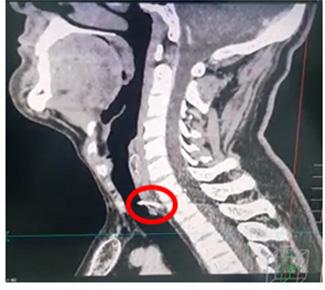

Trauma traqueal por migración de material de osteosíntesis de clavícula

Tracheal trauma due to migration of clavicle osteosynthesis material

Roly Ramos, Cristhian J. Guzmán, Rommer Ortega.............................................................................116-121